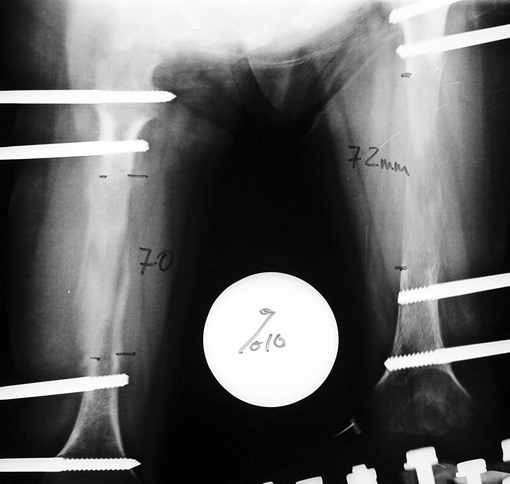

12-14 yaşları arasında Her iki tibiada toplam 10-15cm boy uzatma (iki seviyeli uzatma) Proksimal tibianın varus deformitesini proksimal osteotomi ile düzeltilmesi Distal tibianın varus deformitesi distal osteotomi ile düzeltmesi Distal tibianın varus deformitesi distal osteotomi ile düzeltmesi Boy uzatmanın sonunda lateral kollateral ligamentin gerilmesi Ortalama eksternal fiksasyon tedavi süresi = 8-10 ay